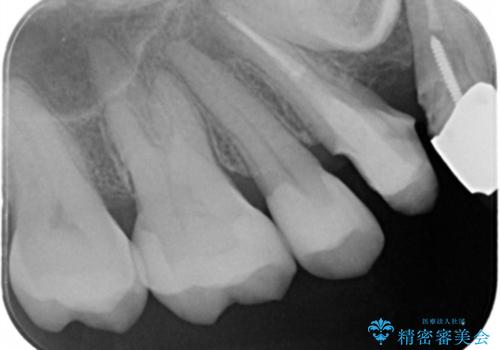

- メタルインレーやりかえ希望の患者様です。

拡大鏡下でメタル、う蝕の除去を行いe-maxインレー(セラミックインレー)で治療しました。

適合の良いe-maxインレーが入りました。

銀の詰め物に比べてセラミックインレーは虫歯の再発のリスクが少なくなります。